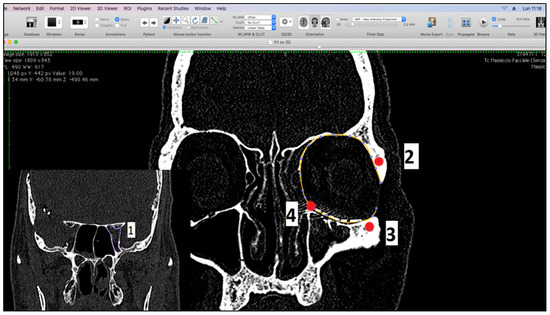

We performed the measurements using Osirix software in semi-automatic and manual mode on CT scans [17,18], on both preoperative and postoperative CT examinations, with slices of 0.5 mm and with the head positioned in its “neutral position”. Preoperative CT was carried out within 24 h of the trauma. We corrected the minimal movement discrepancies using the MPR function of the software with anatomical references in the planes: the Frankfurt horizontal plane, a vertical plane passing between the supraorbital foramen and the maxilla-malar suture of the lower orbital frame, and the tangential horizontal plane to the lower orbital frames. Volumetric analysis after CT orientation was performed on coronal scans in bone cuts. Since the orbital cavity reflects the geographical shape of a cone, with the base at the level of the orbital frames, several reference points have been identified to standardize the measurement procedure which are (1) the optic foramen; (2) the frontal zygomatic suture; (3) the maxillo-malar suture at the level of the lower orbital frame; and (4) the lacrimal canal. The plane passing through points 2, 3, and 4 was considered the base of the cone (Figure 1).

Figure 1.

Measurement landmarks.